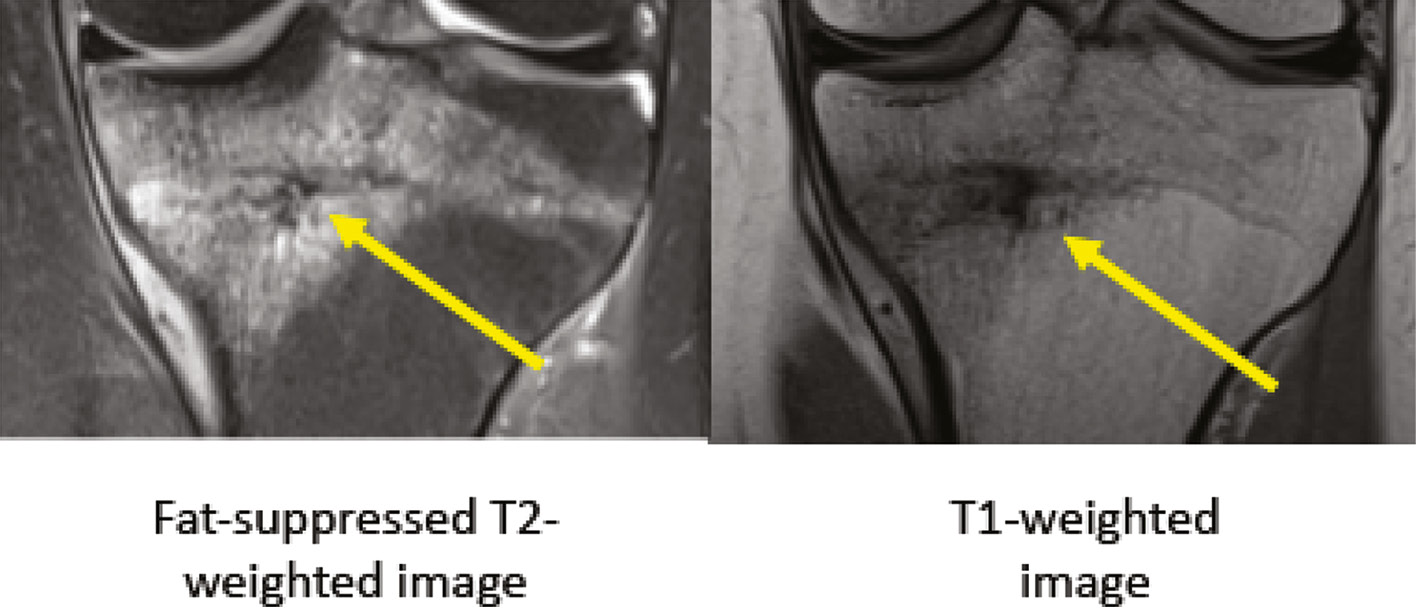

Figure 2. MRI of Fredericson Grade 2 bone stress injury of tibia. Arrow demonstrates marrow edema on fat-suppressed T2-weighted image (normal appearance on T1-weighted image).

jposna20220015_fig2.jpg